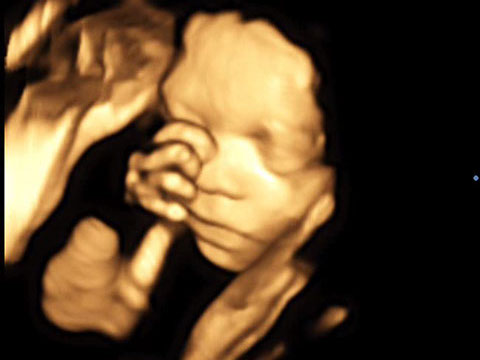

Der 4D-Ultraschall ist eine Methode der Ultraschall-Untersuchung, bei der das Ultraschallgerät ein dreidimensionales Bild des Untersuchungsobjekts in Echtzeit erzeugt.

Er kann als risikofreie Untersuchungsmethode ohne nennenswerte Belastung für Mutter und Kind durchgeführt werden.